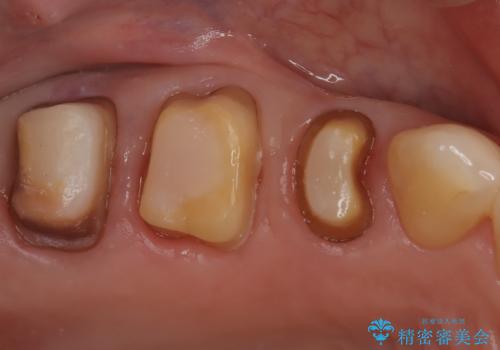

- 右上の奥歯(5番・6番・7番)に入っている銀歯を白くし、お口全体の健康状態を改善したいという主訴でご来院されました。

精密な診査の結果、一番奥の7番目の歯の根の先に、根尖病変(膿の袋)が認められました。そのため、単に被せ物を新しくするだけでなく、まずは土台となる根の状態を整える必要があると判断。右上7番には再発を防ぐための精密根管治療を行い、その後、5番・6番・7番の3本全てを、強度と審美性に優れたセラミッククラウンで修復する計画を立案しました。

セラミッククラウンによる修復 根の状態が安定した後、5番・6番・7番の3本にセラミッククラウンを装着しました。以前のメタルインレーは歯を部分的に覆うものでしたが、今回は歯の破折リスクを抑え、全体を保護するためにフルカバーのクラウンを選択しています。